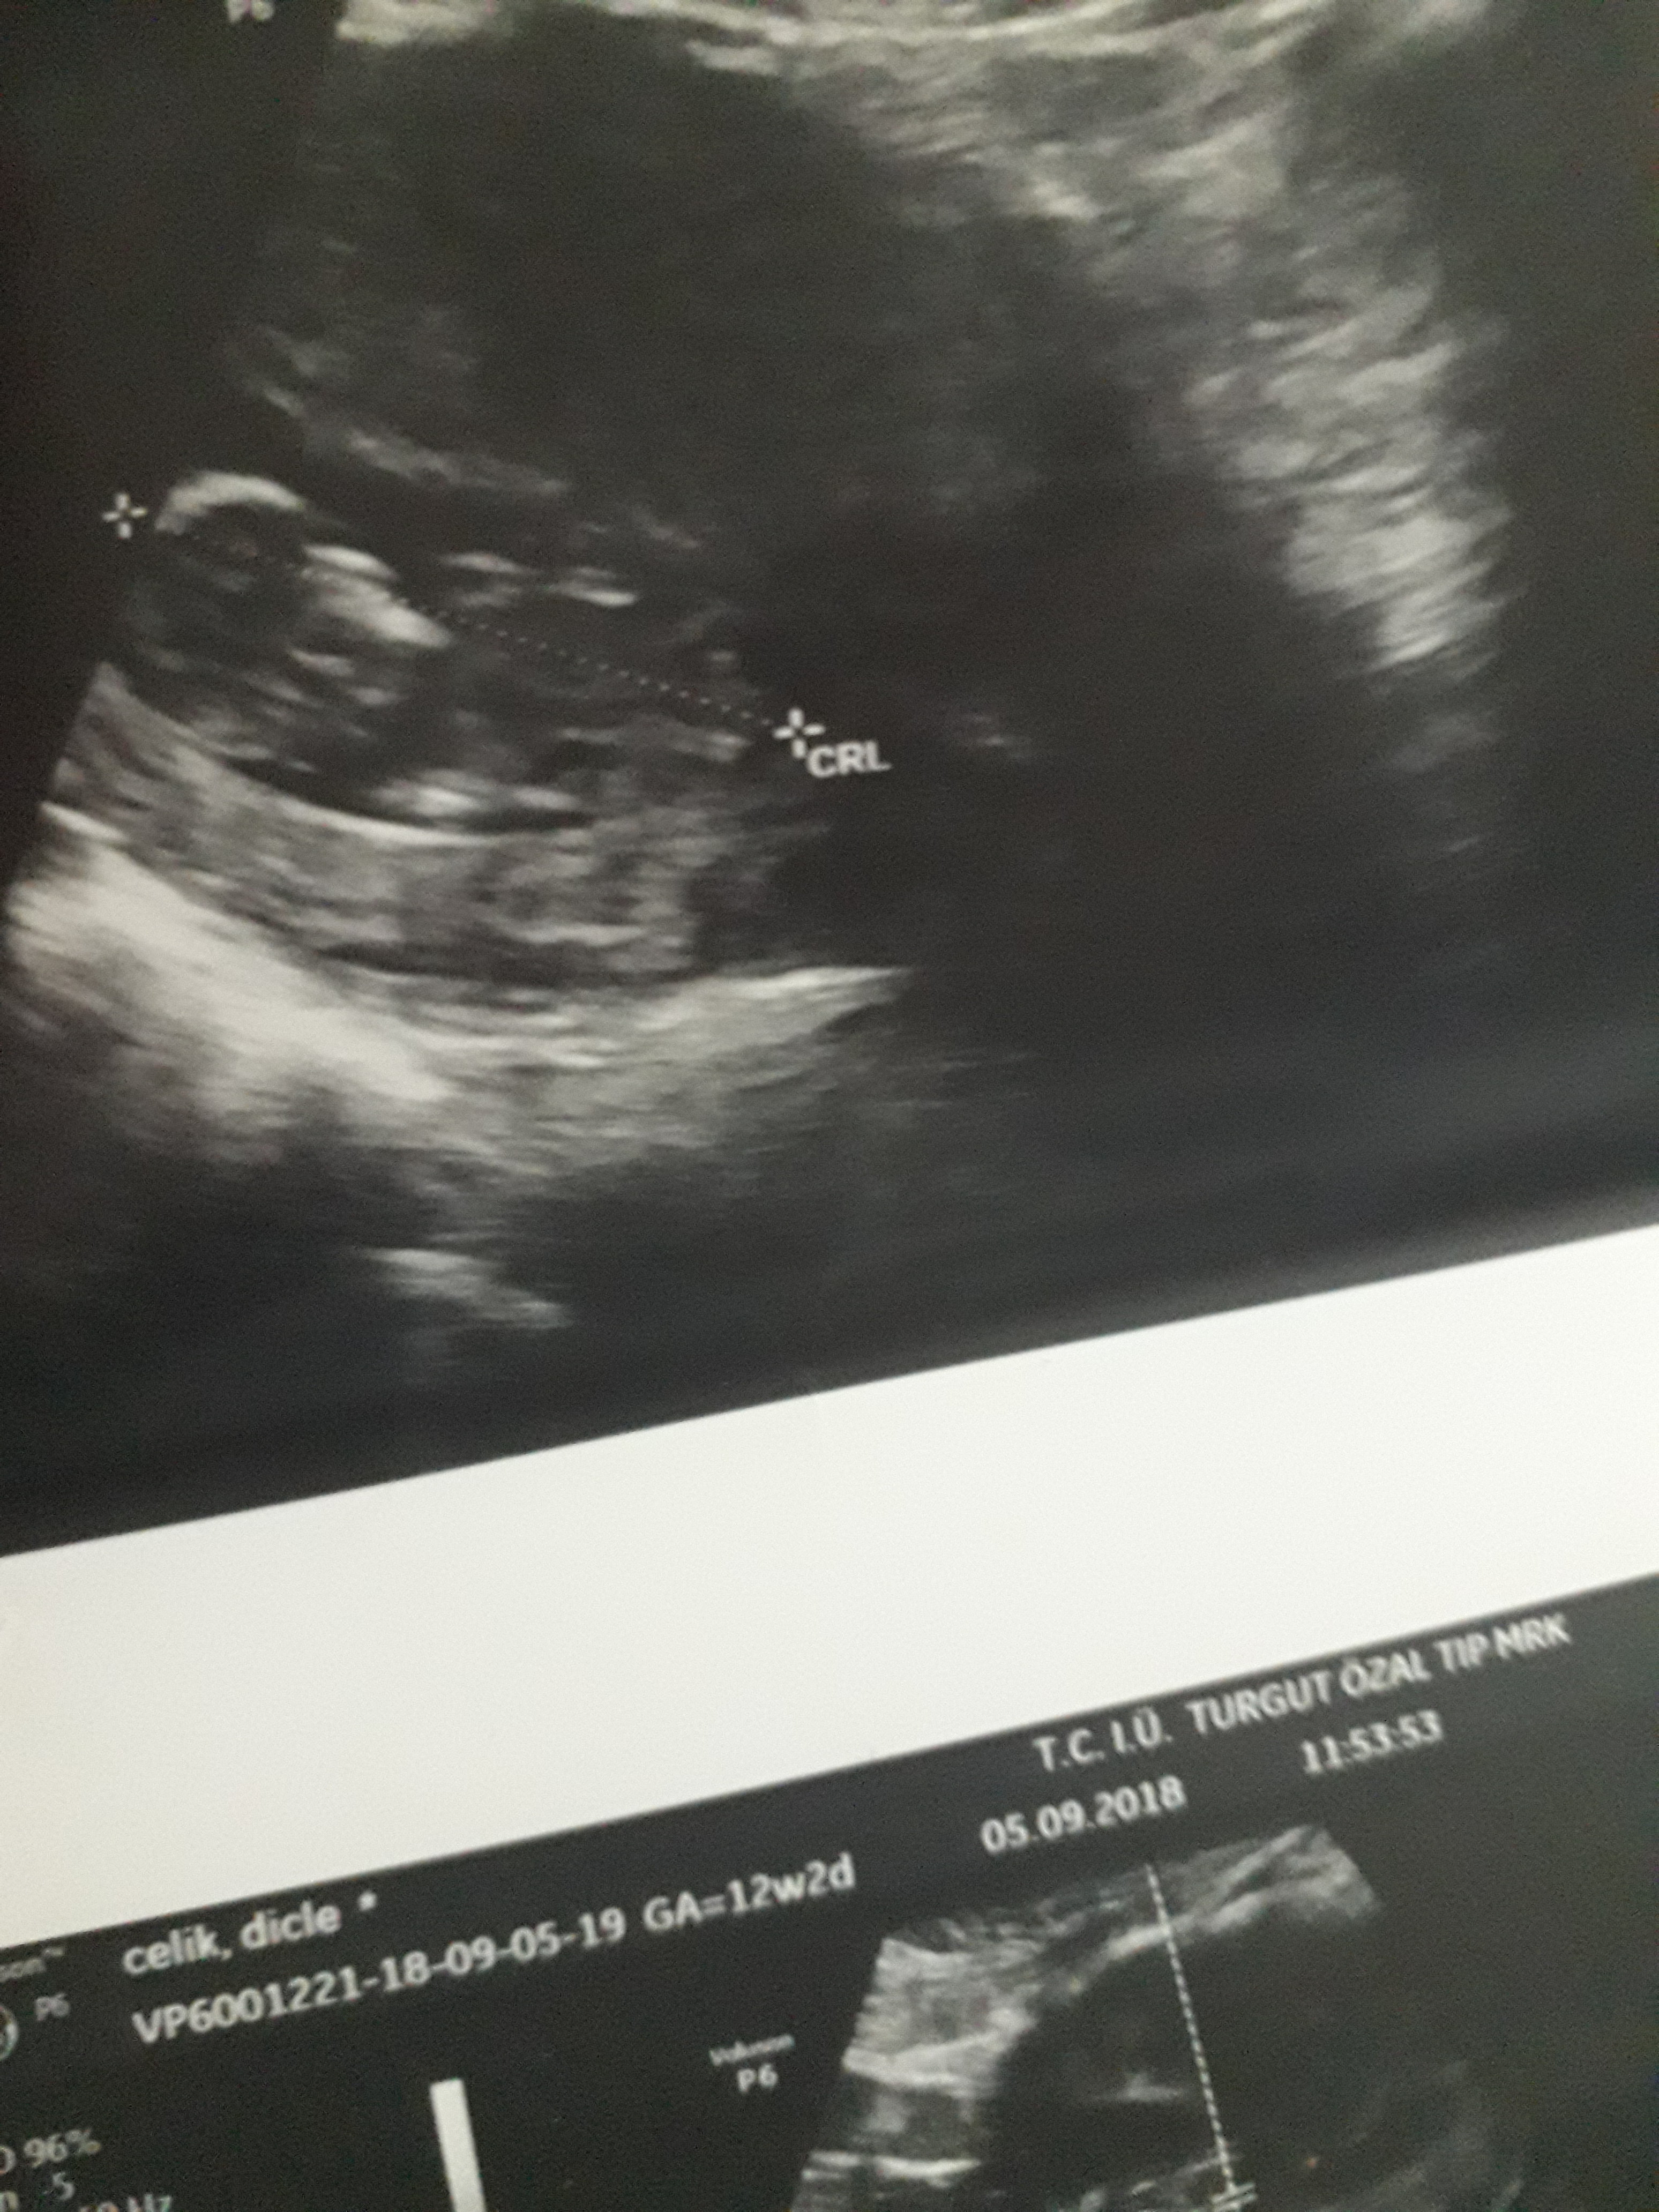

Dun malatyada verildi 12 +4 gunluk lutfen yorumlayin

Dun verildi 12 haftalik lutfen yorumlayin

Görsellerde nub çıkıntısı belli değil . Ultrasonu yapan doktor cinsiyeti hakkında bilgi vermiştir mutlaka ama şunu belirtmeden geçmeyeyim. Bu haftalarda cinsiyet tahmininde yanılma payı çok yüksek 17-19 ve 20 ci haftalarda bebeğin cinsiyetini net olarak öğrenebilirsiniz.